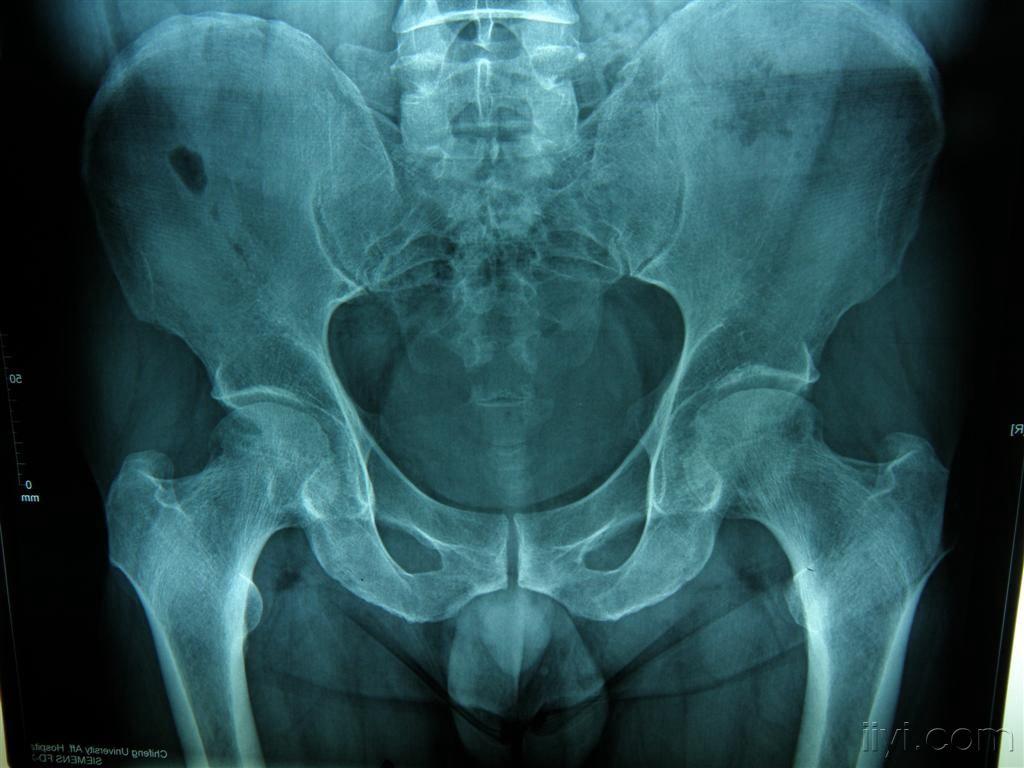

双侧股骨头缺血性坏死-医学影像图